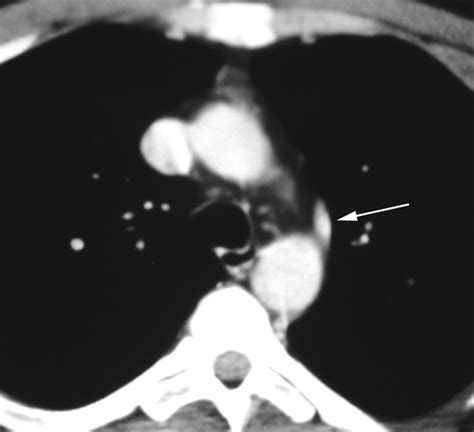

• The Azygos Point (or Teardrop): A dense, teardrop-shaped opacity at the inferior end of the fissure line. This represents the cross-section of the misplaced azygos vein itself.

While standard chest X-rays are usually sufficient for diagnosis, computed tomography (CT) provides a definitive view. On a CT scan, the Vena Azygos Lobe is clearly demonstrated as an isolated pleural-lined segment of lung tissue separated from the rest of the right upper lobe by the azygos fissure.

• Lung Nodules: The "teardrop" shadow of the azygos vein itself can be mistaken for a solitary pulmonary nodule or a mass.